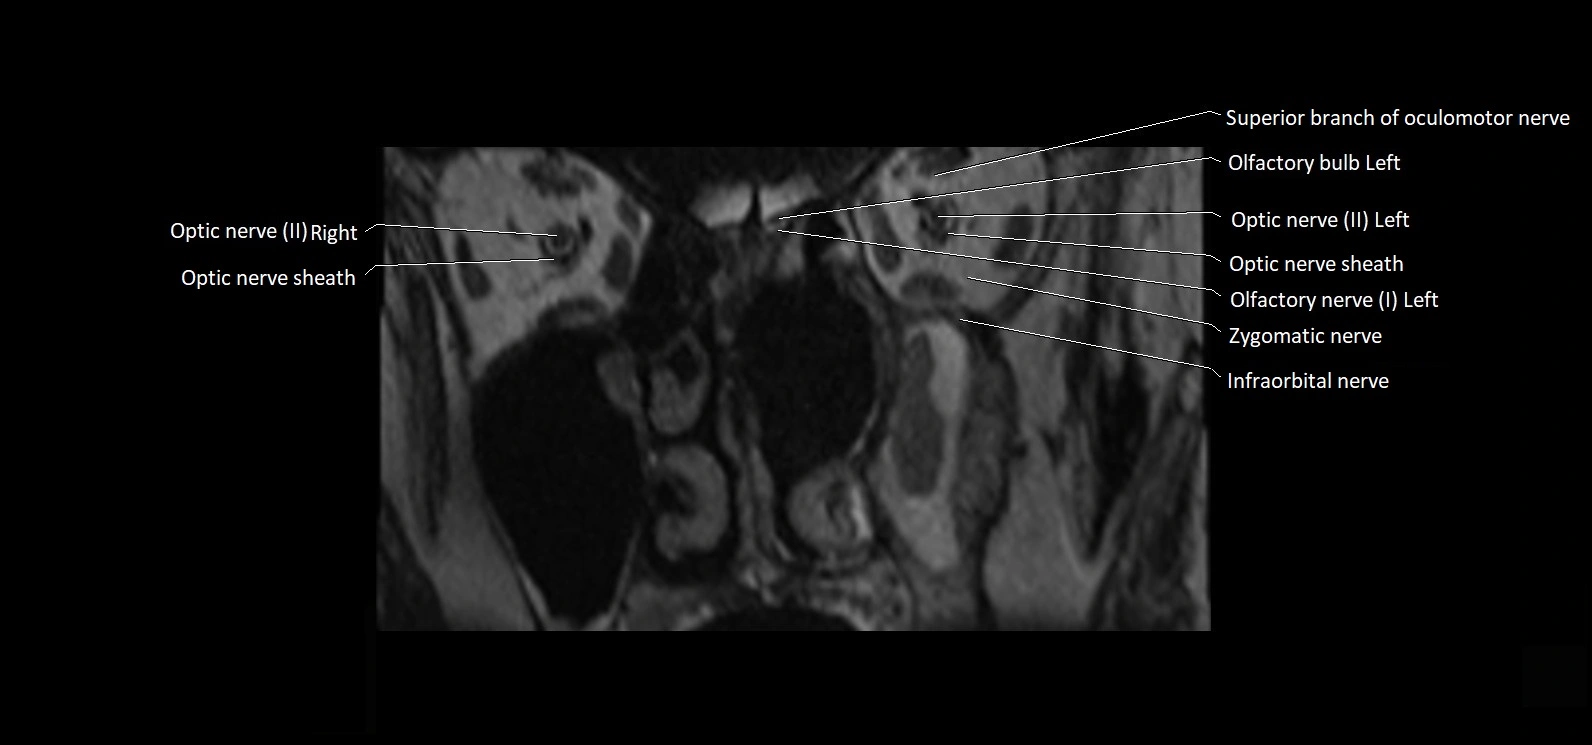

MRI Appearance

• The abducens nerve is a small, thin, linear structure

• Best visualized on high-resolution T2-weighted 3D MRI sequences (e.g., FIESTA or CISS)

• Seen as a hypointense (dark) line running from the brainstem at the pontomedullary junction, traversing the prepontine cistern, and entering Dorello’s canal under the petrosphenoidal ligament, then into the cavernous sinus, and finally the orbit

• May be challenging to visualize in standard MRI due to its small size

• Pathology may be inferred by absence, displacement, or enhancement of the nerve

MRI images

image